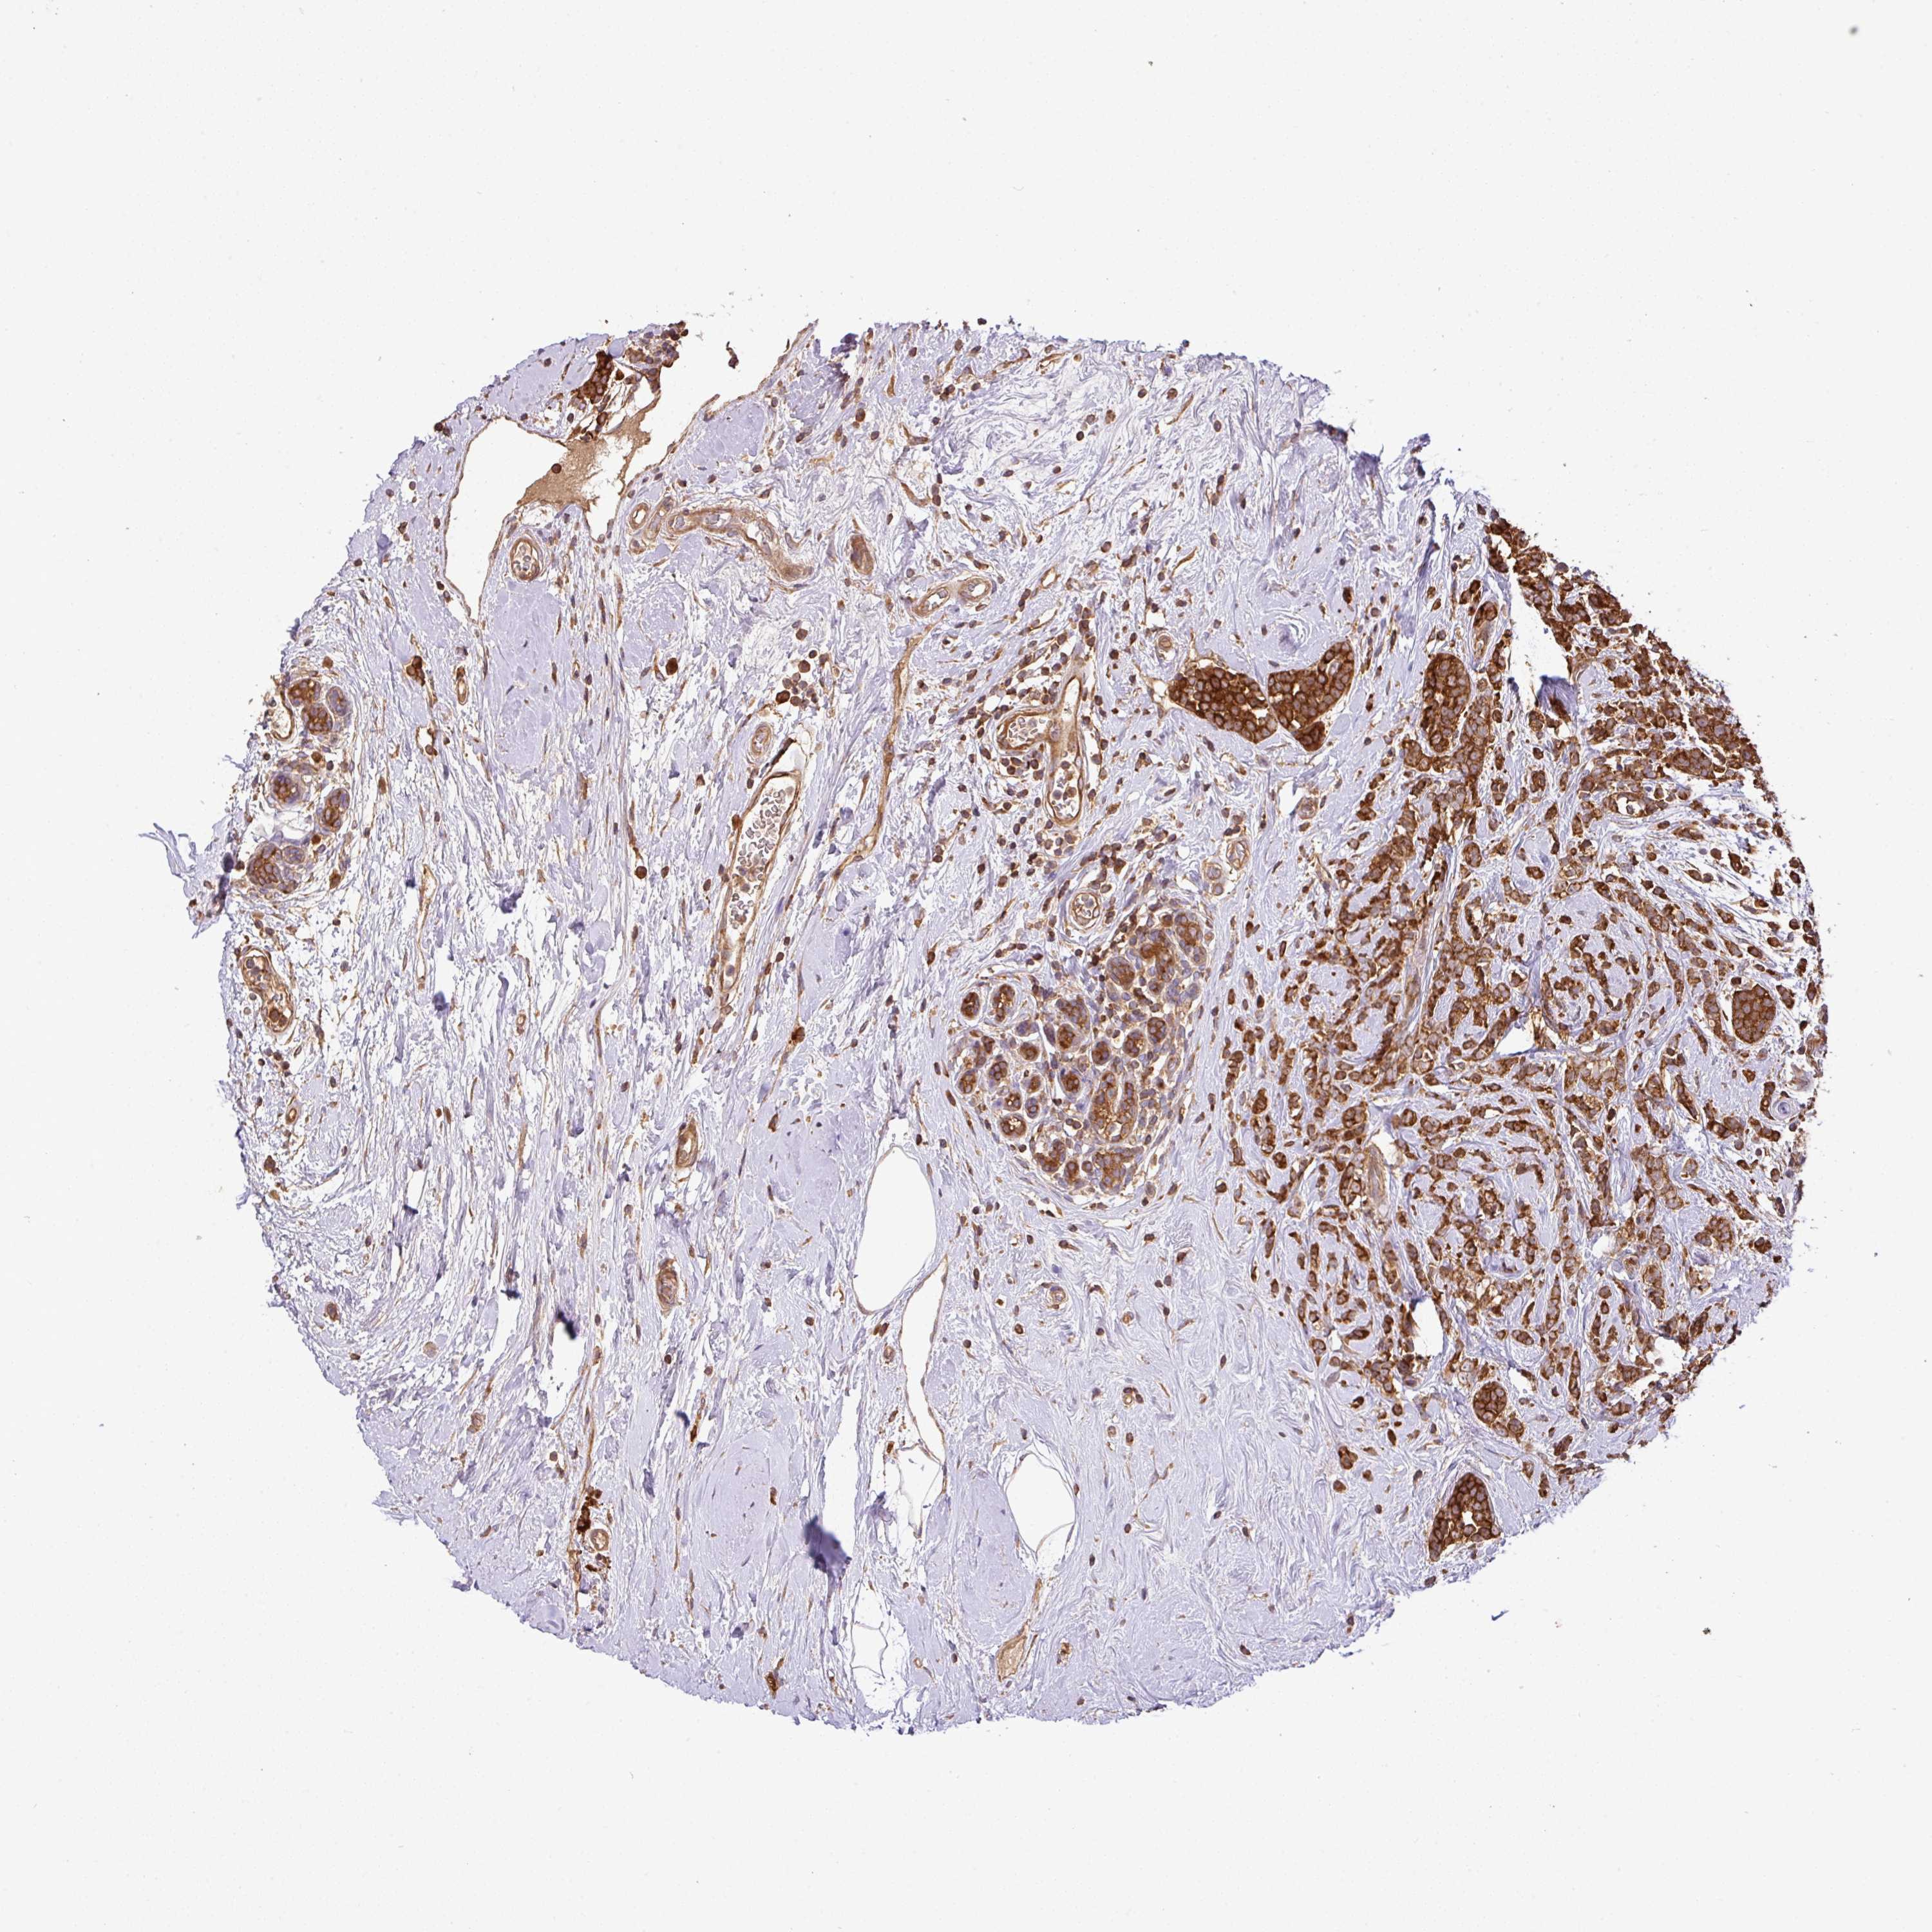

CANCER BREAST CANCER Show tissue menu

BRCA TCGA BRCA VALIDATION PROTEIN EXPRESSION

ANTIBODIES

AND

VALIDATION